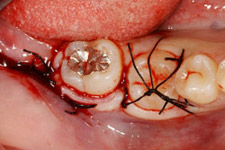

移植中の様子

第一大臼歯の抜歯後2週間で移植を行いました。

移植のために抜歯された右下の親知らず。歯根がまだ完成していない若い歯です。